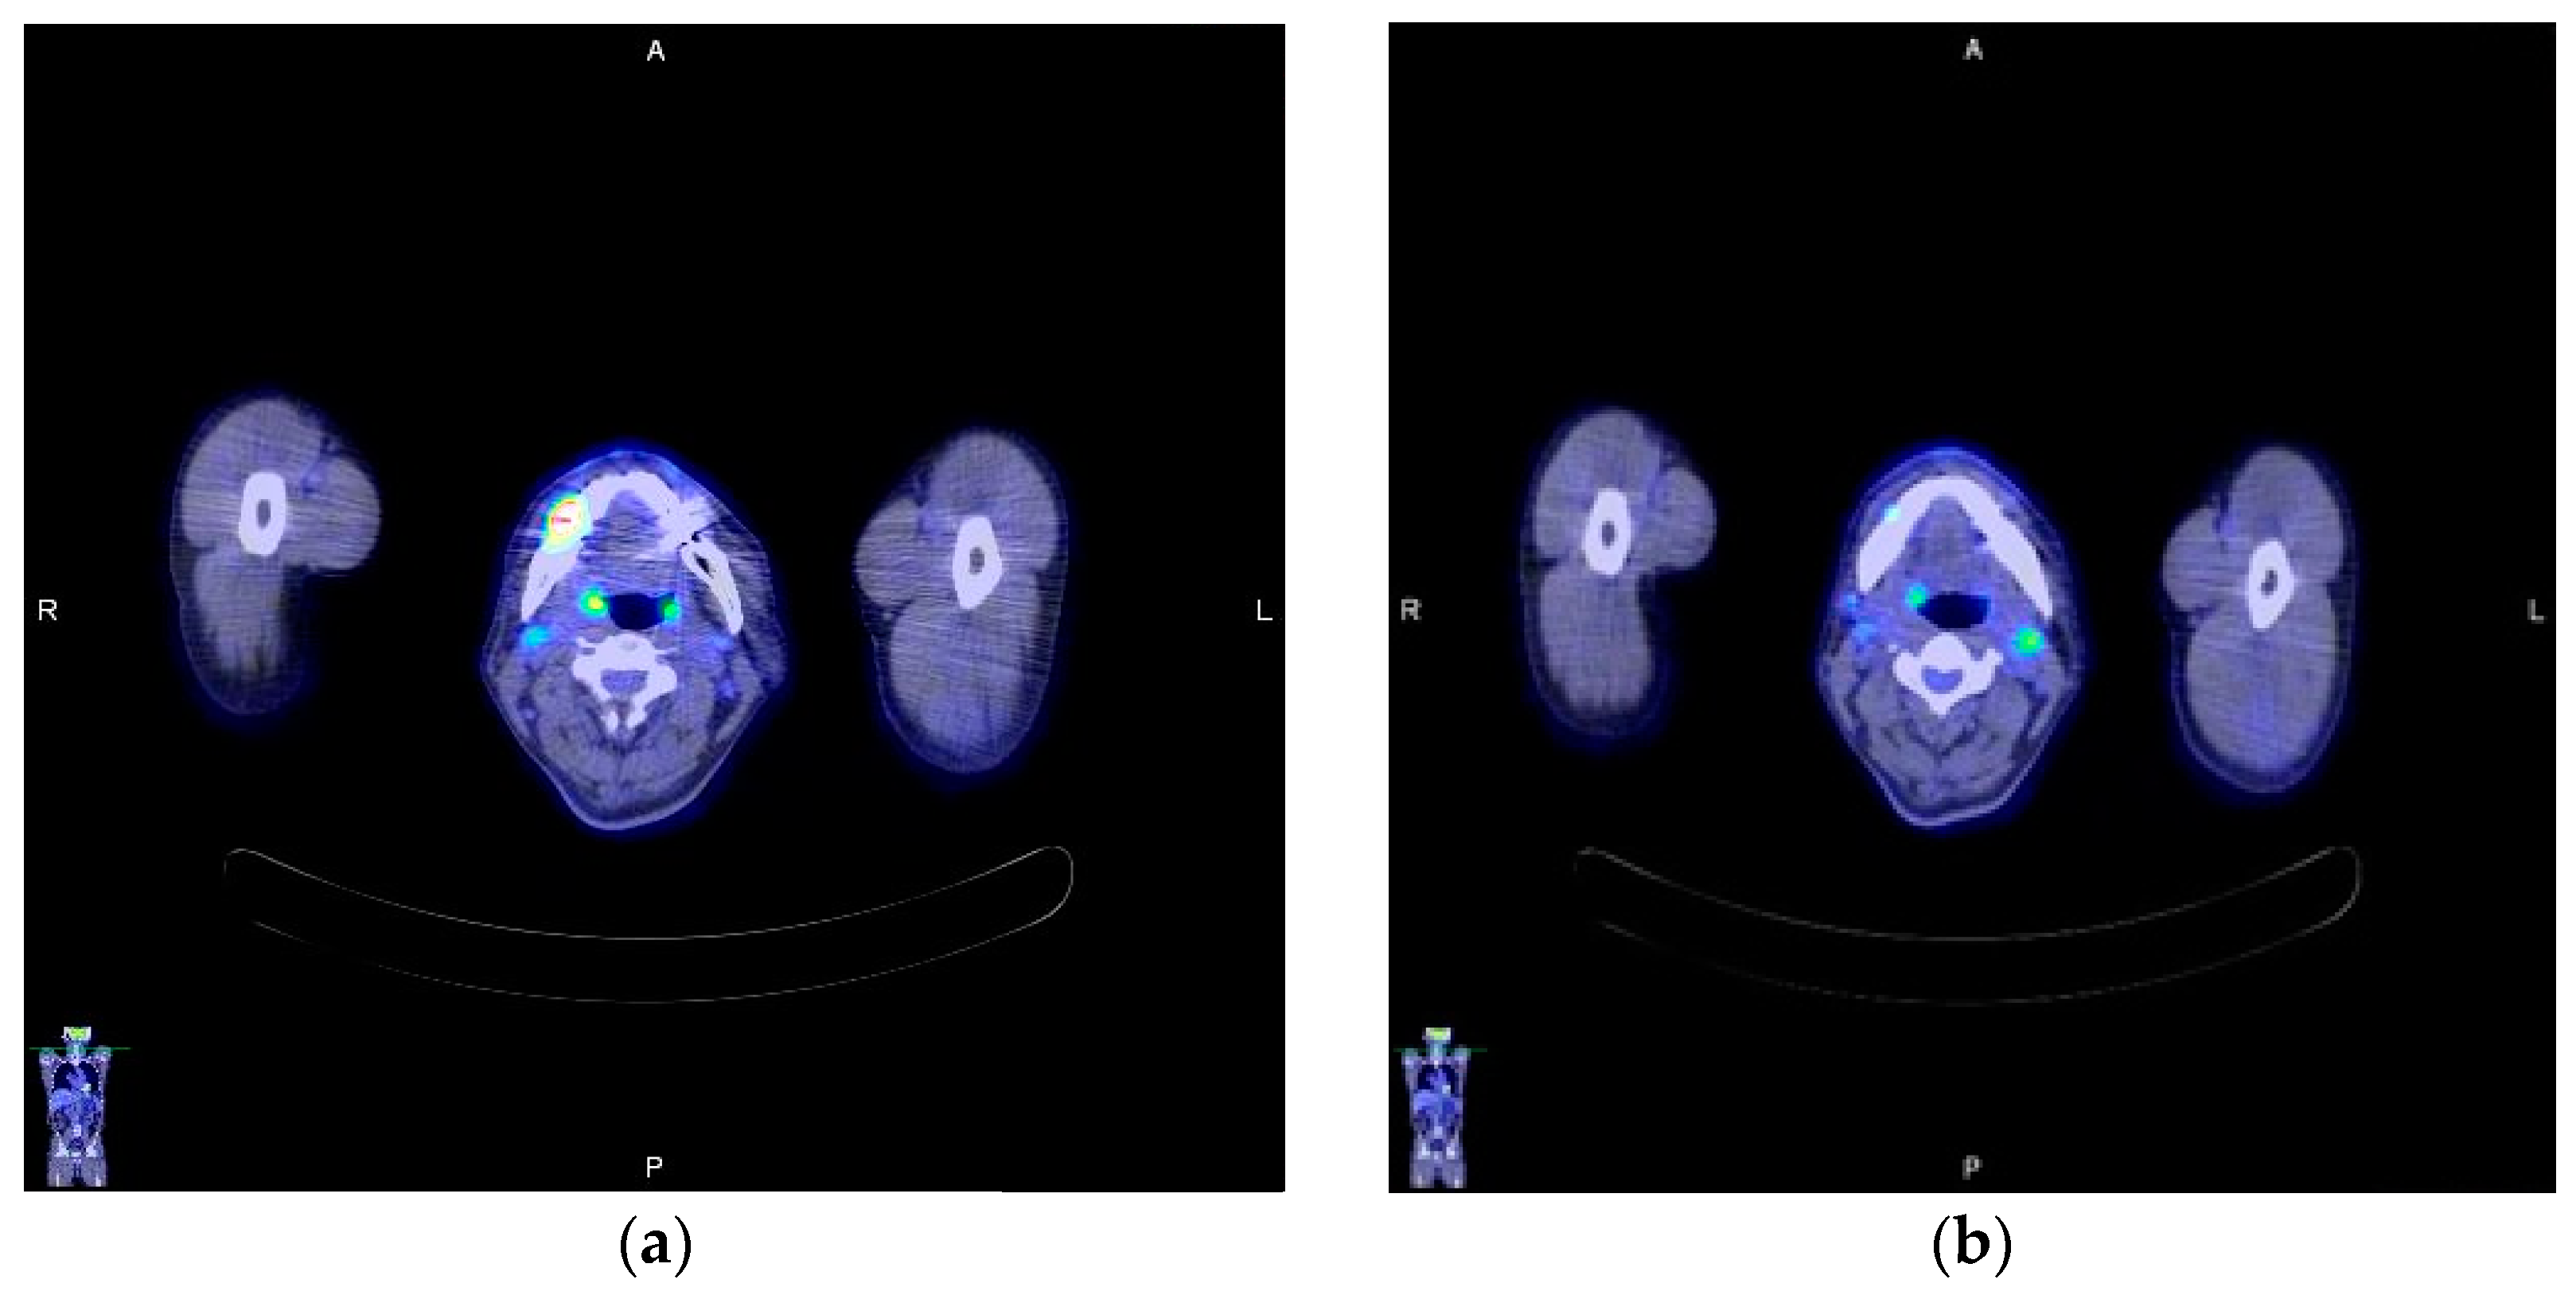

2. Case Report